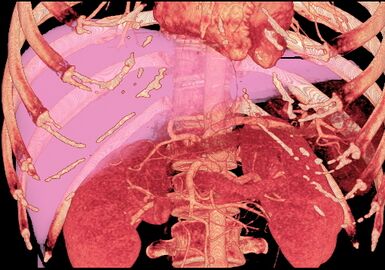

With the recent advances of noninvasive imaging, living liver donors usually have to undergo imaging examinations for liver anatomy to decide if the anatomy is feasible for donation. The evaluation is usually performed by multidetector row computed tomography (MDCT) and magnetic resonance imaging (MRI). MDCT is good in vascular anatomy and volumetry. MRI is used for biliary tree anatomy. Donors with very unusual vascular anatomy, which makes them unsuitable for donation, could be screened out to avoid unnecessary operations.